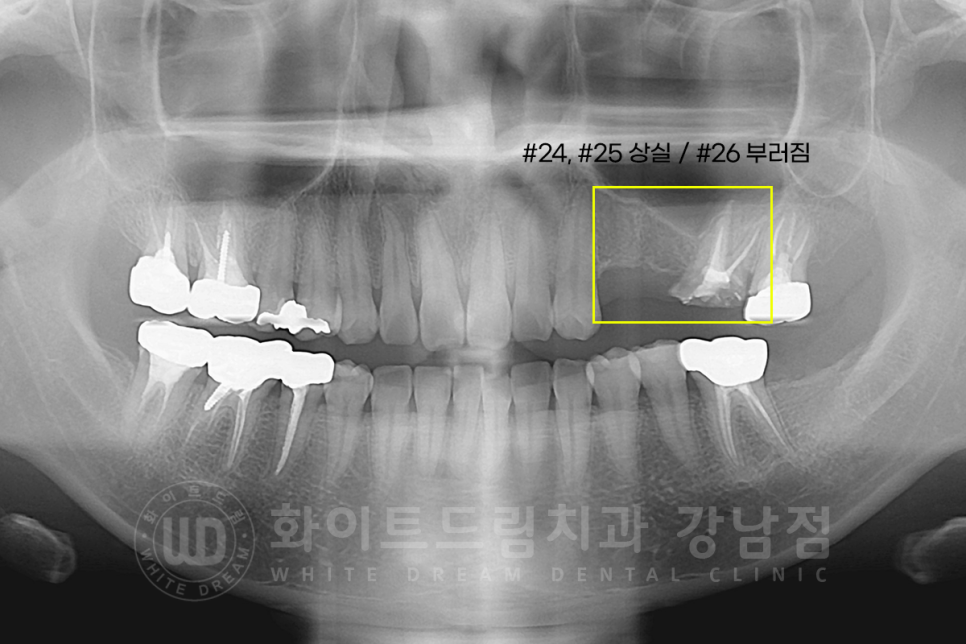

20번대 치아가 다수 상실되고 부러진 상태로 내 원하신 분입니다.

부러진 26번 치아는 원래 크라운으로 되어있던 치아였는데 크라운 내부 2차 충치가 심하게 진행되어 있어

치아가 부러진 상태였습니다.

▲ 뿌리만 남아있던 부러진 26번 치아입니다.

크라운이 있었던 자리에 심한 충치가 확인됩니다.

26번 발치 + 임플란트 식립 / 상실치 부분도 임플란트 식립을 진행하기로 했는데요.

3D-CT를 이용하여 확인하니 잇몸뼈의 두께가 임플란트를 식립하기에는 많이 모자란 상태였기에

상악동 거상술(Lateral)을 진행하기로 했습니다.